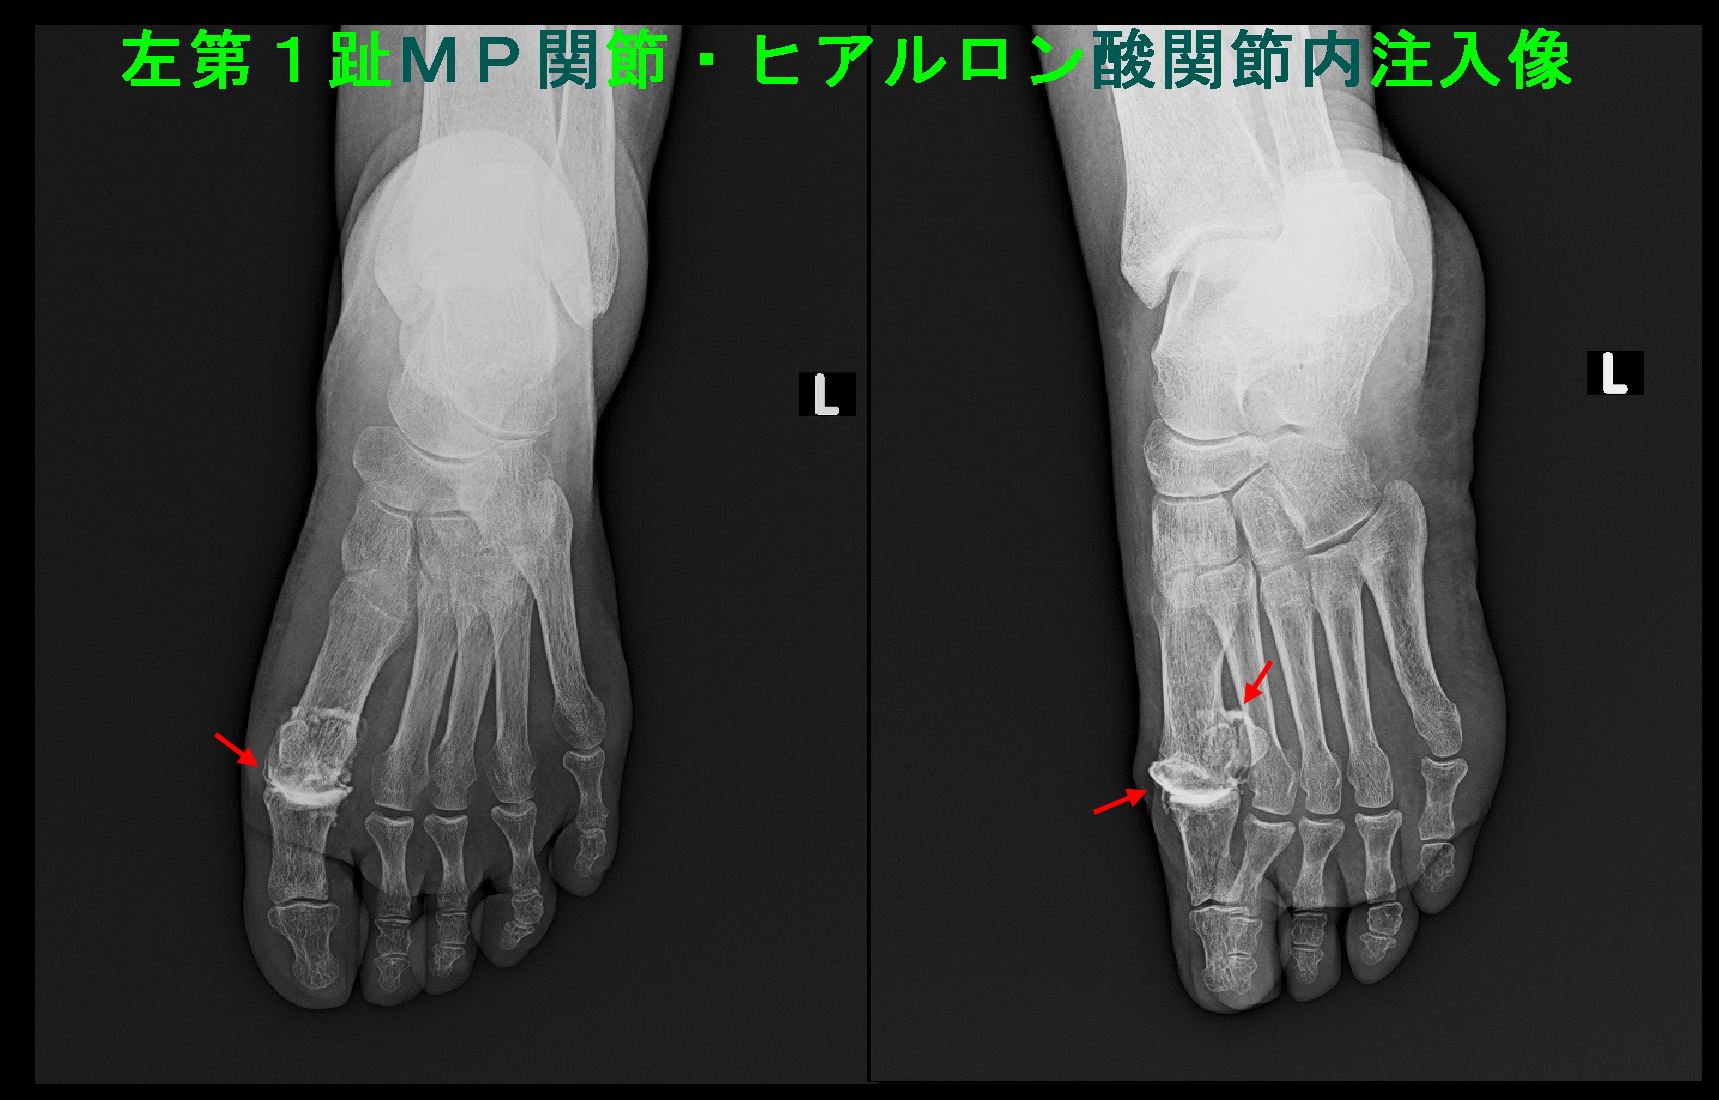

67才女RA Xp3.jpg

令和7年10月28日からヒアルロン酸の関節内注入を開始し、11月25日に5回目の注入を行いました。以後は2週に1回で継続しましたが、令和8年1月6日には痛みはVAS0~1ということでヒアルロン酸の関節内注入は経過をみることにしました。

このリウマチの女性の第1足指MP関節へのヒアルロン酸の関節内注入の適応は、他の同足指MP関節へのヒアルロン酸の関節内注入で劇的な改善がえられた患者さんがいたことで適応してみたのです。

ステロイドの関節内注入では治癒にもっていくことができないと判断し治療方針を変えて、注入薬剤をステロイドから変形性膝関節症で適応されている変形老化予防のヒアルロン酸製剤に変更して、1週間に1回連続5回関節内注入してみましょうと提案し、了承をえました。